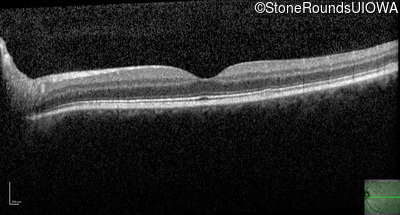

AR Stargardt Disease (IIA)

Age at visit: 32 years

Diagnosis & molecular findings

Disease Gene Allele 1 variant(s) Allele 2 variant(s) Inheritance mode

AR Stargardt Disease ABCA4 IVS30+1321 A>G Asn965Ser AAT>AGT AR